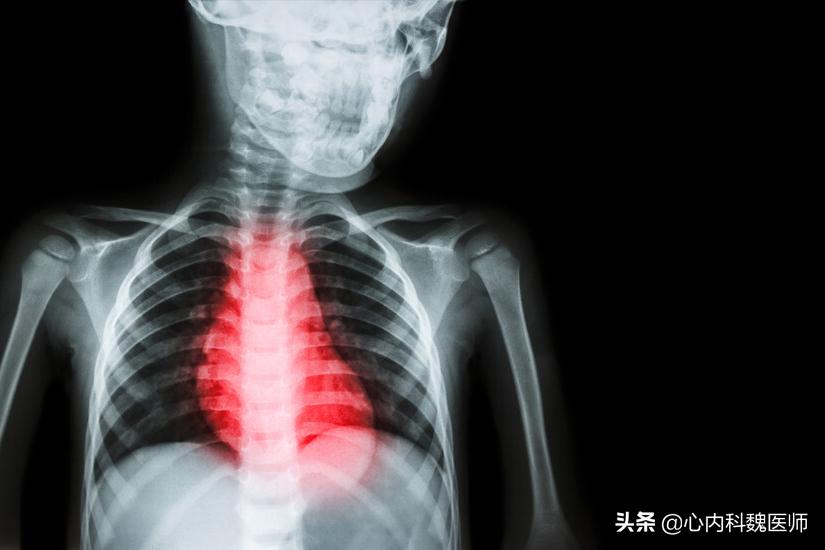

一旦被甲亢盯上,可造成身体多器官组织的危害。甲状腺激素长期过量释放会导致心跳速率增加、心脏增大、早搏、心房纤颤、心力衰竭、心绞痛等甲亢性心脏病,而且随着病程的增加,发病率越高;还会造成转氨酶升高、肝功能受损、肝肿大、极度消瘦、胃肠功能紊乱等消化系统的危害;性欲减退、月经紊乱、怀孕后胎儿发育不良、早产等生殖系统损害;躁狂症、抑郁症、全身震颤、精神分裂症等神经系统损害;血小板减少、贫血等造血系统的损害……

因此,对于一饿就心慌、手抖这类症状一定要及时就医不可大意,一旦确诊为甲亢要积极配合医生治疗。 目前其治疗措施主要分为三种,药物治疗、放射性碘131同位素以及手术治疗, 其中病症较轻的患者推荐常规药物对症治疗;而当药物治疗效果达不到理想水平或是腺体已出现明显肿大则推荐采用放射治疗;当腺体已压迫邻居组织或器官时,视情况严重程度来选择手术治疗。